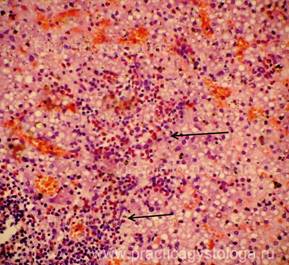

Рис. 1, 2. Картина очагового острого гнойного межуточного миокардита: очаговая и очагово-диффузная инфильтрация стромы миокарда сегментоядерными нейтрофильными лейкоцитами в различной степени выраженности, лейкоциты как чётко контурирующиеся, так и в состоянии распада. Отдельные кардиомиоциты и мелкие их пучки в состоянии некроза. Окраска: гематоксилин-эозин. Увеличение х100, х250.